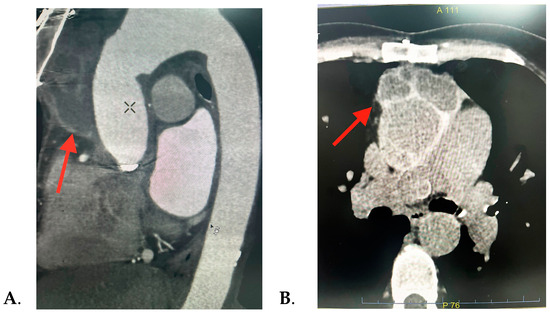

| -prolonged febrile syndrome -vertigo -pale skin -closing click in the aortic area | Mother died at 36 y (spontaneous carotid artery dissection) | Bentall procedure (for acute DeBakey type I aortic dissection) | -elevated ESR -elevated C-reactive protein -positive procalcitonin -negative blood cultures -elevated phase I and phase II IgG and IgM | -mechanical prosthesis in aortic position -12 mm echo-dense mass surrounding the ascending aorta | 2 years | Medical: -antibiotics: Doxycycline (100 mg/bid) and Hydroxychloroquine (200 mg/tid) -Acenocumeral 4 mg -Furosemide/Spironolactone 20/50 mg/day Surgical: removal of the periaortic hematoma |